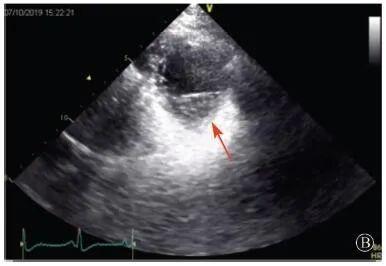

B:胸骨旁左室短轴切面心尖水平,可见心肌肌小梁增多,其内可见隐窝(箭头所示)

图3 患者入院后超声心动图